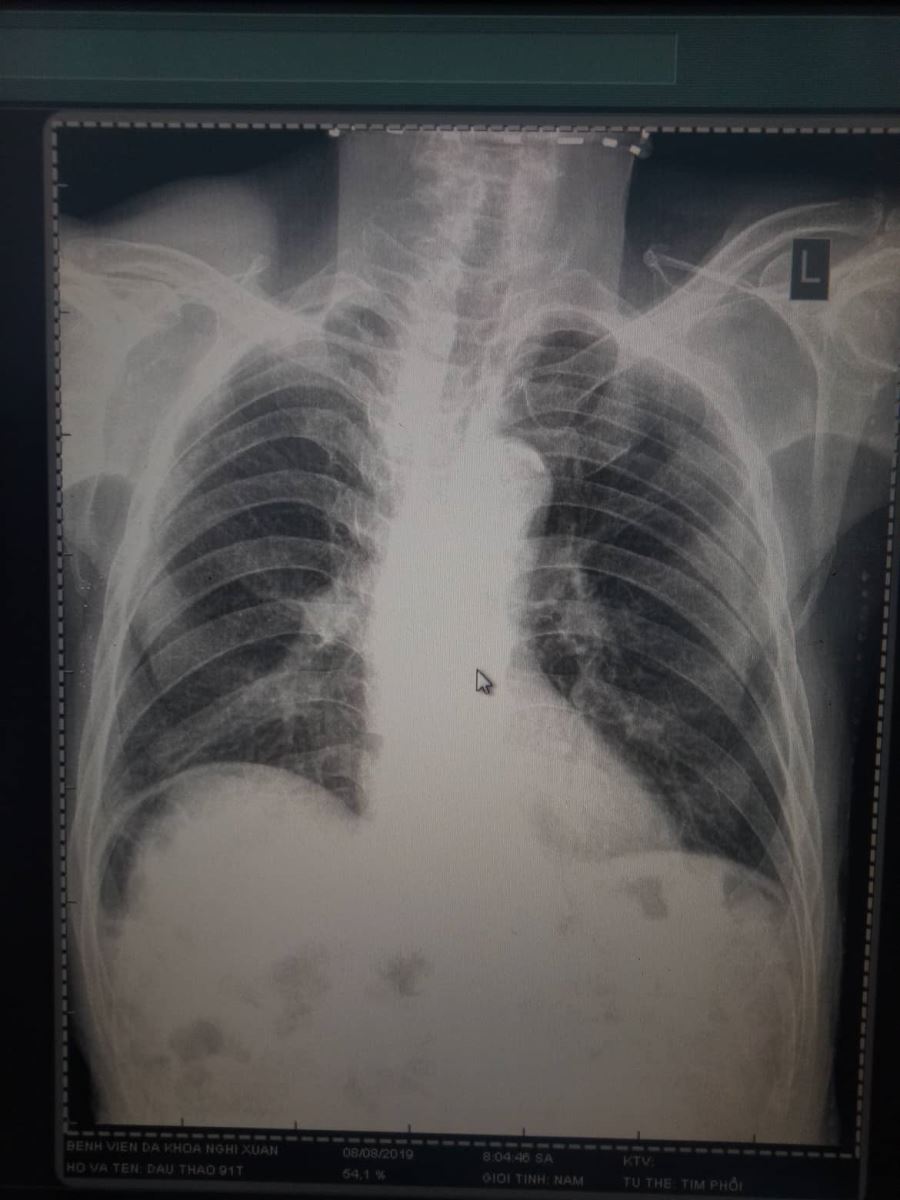

Nhân một trường hợp dấu hiệu Chilaiditi của bệnh nhân Đ.T, 91 tuổi thăm khám tại bệnh viện Đa Khoa Nghi Xuân. Dấu hiệu Chilaiditi được cho là một dấu hiệu hiếm gặp với xác xuất phát hiện qua phim chụp XQ bụng đứng là 0,1% có thể tăng lên đến 1% tùy theo độ tuổi.

Dấu hiệu Chilaiditi được đặt theo tên của bác sĩ X quang Hy Lạp Demetrius Chilaiditi, người đầu tiên mô tả, khi đang làm việc ở Vienna năm 1910. Là một tình trạng hiếm gặp, gây đau, khi một đoạn ruột già (thường là đại tràng ngang) di chuyển và bị kẹt giữa cơ hoành và gan, dấu hiệu này có thể được quan sát thấy trên phim X quang bụng đứng hoặc tim phổi thẳng.

Hinh ảnh XQuang có dấu hiệu về Chilaiditi

Bệnh nhân 91 tuổi, đến khám với triệu chứng đau tức vùng thượng vị, sau khi chụp XQ thấy hình ảnh như hình trên, xét nghiệm cho thấy công thức máu bình thường, amilaza trong giới hạn cho phép. Trên siêu âm, ghi nhận không khảo sát được gan qua mặt cắt liên sường do vướng hơi và không ghi nhận bất thường nào khác. Bệnh nhân được chẩn đoán với dấu hiệu Chilaiditi trên phim chụp XQ và nhập viện theo dõi. Sau 2 ngày, toàn trạng bệnh nhân ổn định, được tư vấn kỹ về các nguy cơ biến chứng và ra viện.

Chilaiditi là một tình trạng hiếm gặp trong đó việc chẩn đoán dễ nhầm lẫn với các bệnh lý cấp cứu ngoại khoa nghiêm trọng như thủng tạng rỗng, do đó cần cẩn thận trong thăm khám nhất là trong các trường hợp có các dấu hiệu lâm sàng. Dấu hiệu “Chilaiditi” không cần điều trị. Tuy nhiên, điều trị đôi khi được yêu cầu trong trường hợp có triệu chứng, chẳng hạn như đau bụng, táo bón, nôn mửa, suy hô hấp, biếng ăn, hoặc tắc nghẽn. Các trường hợp đó được gọi là hội chứng Chilaiditi và không phải của dấu hiệu Chilaiditi. Việc điều trị hội chứng Chilaiditi thường là không phẫu thuật và bao gồm nghỉ ngơi tại giường, bổ sung chất lỏng, giải nén thông mũi dạ dày, thụt, thuốc tẩy, chế độ ăn uống nhiều chất xơ, và làm mềm phân. Dấu hiệu của Chilaiditi gây khó chịu ở bụng nhẹ đến tắc ruột liên tục đòi hỏi phải can thiệp phẫu thuật. Phẫu thuật điều trị, chẳng hạn như thủ thuật cắt bỏ ruột kết, cố định ruột, và cố định gan, cũng có thể được yêu cầu trong trường hợp hiếm hoi.